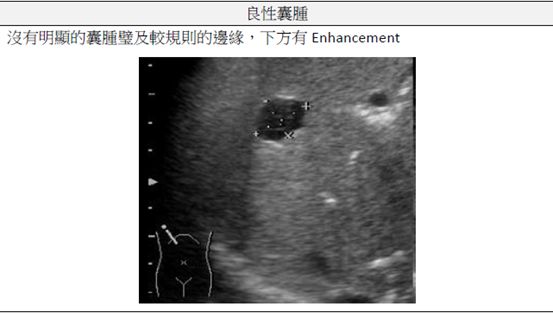

(B)超音波影像中,囊腫後方回音會增強

C.囊腫邊緣清晰且光滑

因為通過低衰減物質超音波能量衰減少,所以有後方回音增強現象